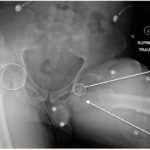

The initial radiograph of the pelvis revealed bilateral hip dislocations. Small bony fragments were noted in the right hip joint, suggestive of an underlying fracture. The sacroiliac joints and the pelvic ring were intact. In the emergency department, bilateral hip reductions were performed using the Captain Morgan technique.1 The post-reduction film showed reduction of the bilateral hip dislocations with extensive comminuted and displaced fractures of the right and left acetabula.